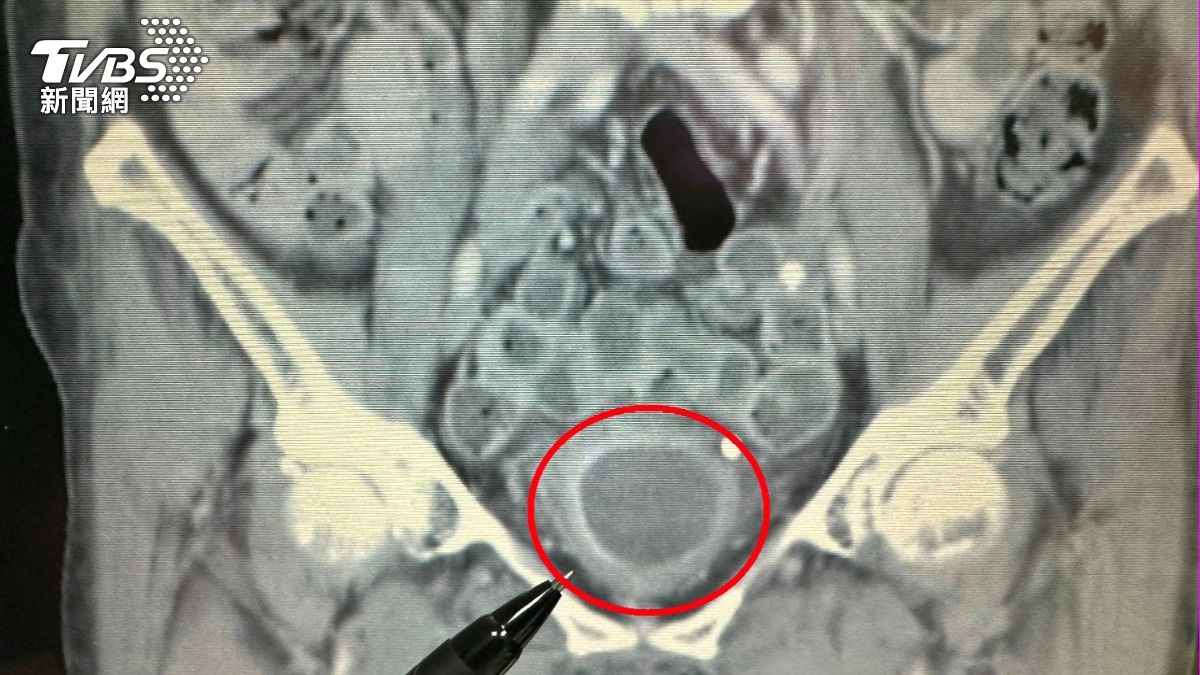

76歲的陳女士因近一個月持續出現無痛性血尿症狀,而到醫院就醫。經醫師檢查發現,她雖然有明顯的血尿狀況,但未出現發炎反應、尿路結石、腎水腫或腎腫瘤的情況,且腎功能正常。進一步安排靜脈注射腎盂攝影,顯示在膀胱內有大片陰影,續以膀胱鏡檢查,發現膀胱內有一個約7X6公分的巨大腫瘤。所幸,經醫師安排「經尿道膀胱腫瘤刮除手術」後,順利清除腫瘤,也成功保留膀胱,目前恢復良好並定期回診追蹤。

大千綜合醫院泌尿科醫師陸兆明表示,此位病人的膀胱腫瘤體積頗大,已佔據未漲尿時的膀胱將近1/2空間,但因為腫瘤細胞尚未侵犯到膀胱外圍,也沒有骨盆淋巴結轉移的情況,因此適用「經尿道膀胱腫瘤刮除手術」來處理腫瘤。此手術透過膀胱內視鏡,由尿道進入膀胱來逐步刮除腫瘤,不僅可得到足夠的檢體,來檢查癌細胞有無侵犯深層肌肉,並將肉眼可見的病灶加以切除;同時,病人腹部無傷口,且可保留膀胱,繼續保有儲尿和排尿的功能,不需另裝人工膀胱,就能維持正常生活品質。另外,病人手術後恢復快、併發症少、安全性較高,對於初期膀胱癌的病人而言是一適合的治療選擇。